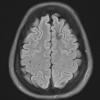

VASCULAR

Cavernous Angioma (13)